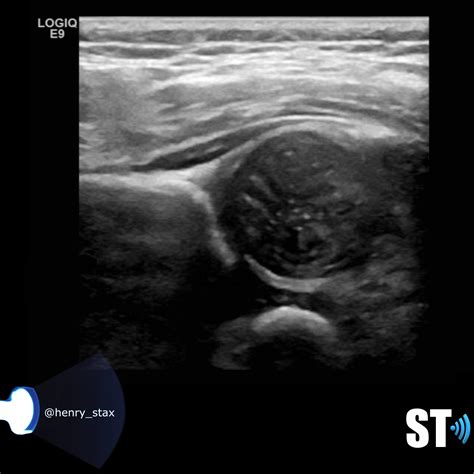

The primary goal of an Infant Hip Ultrasound is to detect developmental dysplasia of the hip (DDH), a condition where the hip joint does not form properly. DDH can range from a shallow acetabulum (the socket part of the hip joint) to a complete dislocation of the femoral head (the ball part of the hip joint). Early detection and treatment of DDH are essential to prevent long-term complications, such as arthritis and limited mobility.

The results of an Infant Hip Ultrasound are interpreted by a radiologist or orthopedic specialist who is trained in pediatric imaging. The images are evaluated for several key factors, including:

• The shape and depth of the acetabulum

• The position of the femoral head within the acetabulum

• The presence of any abnormalities or dislocations